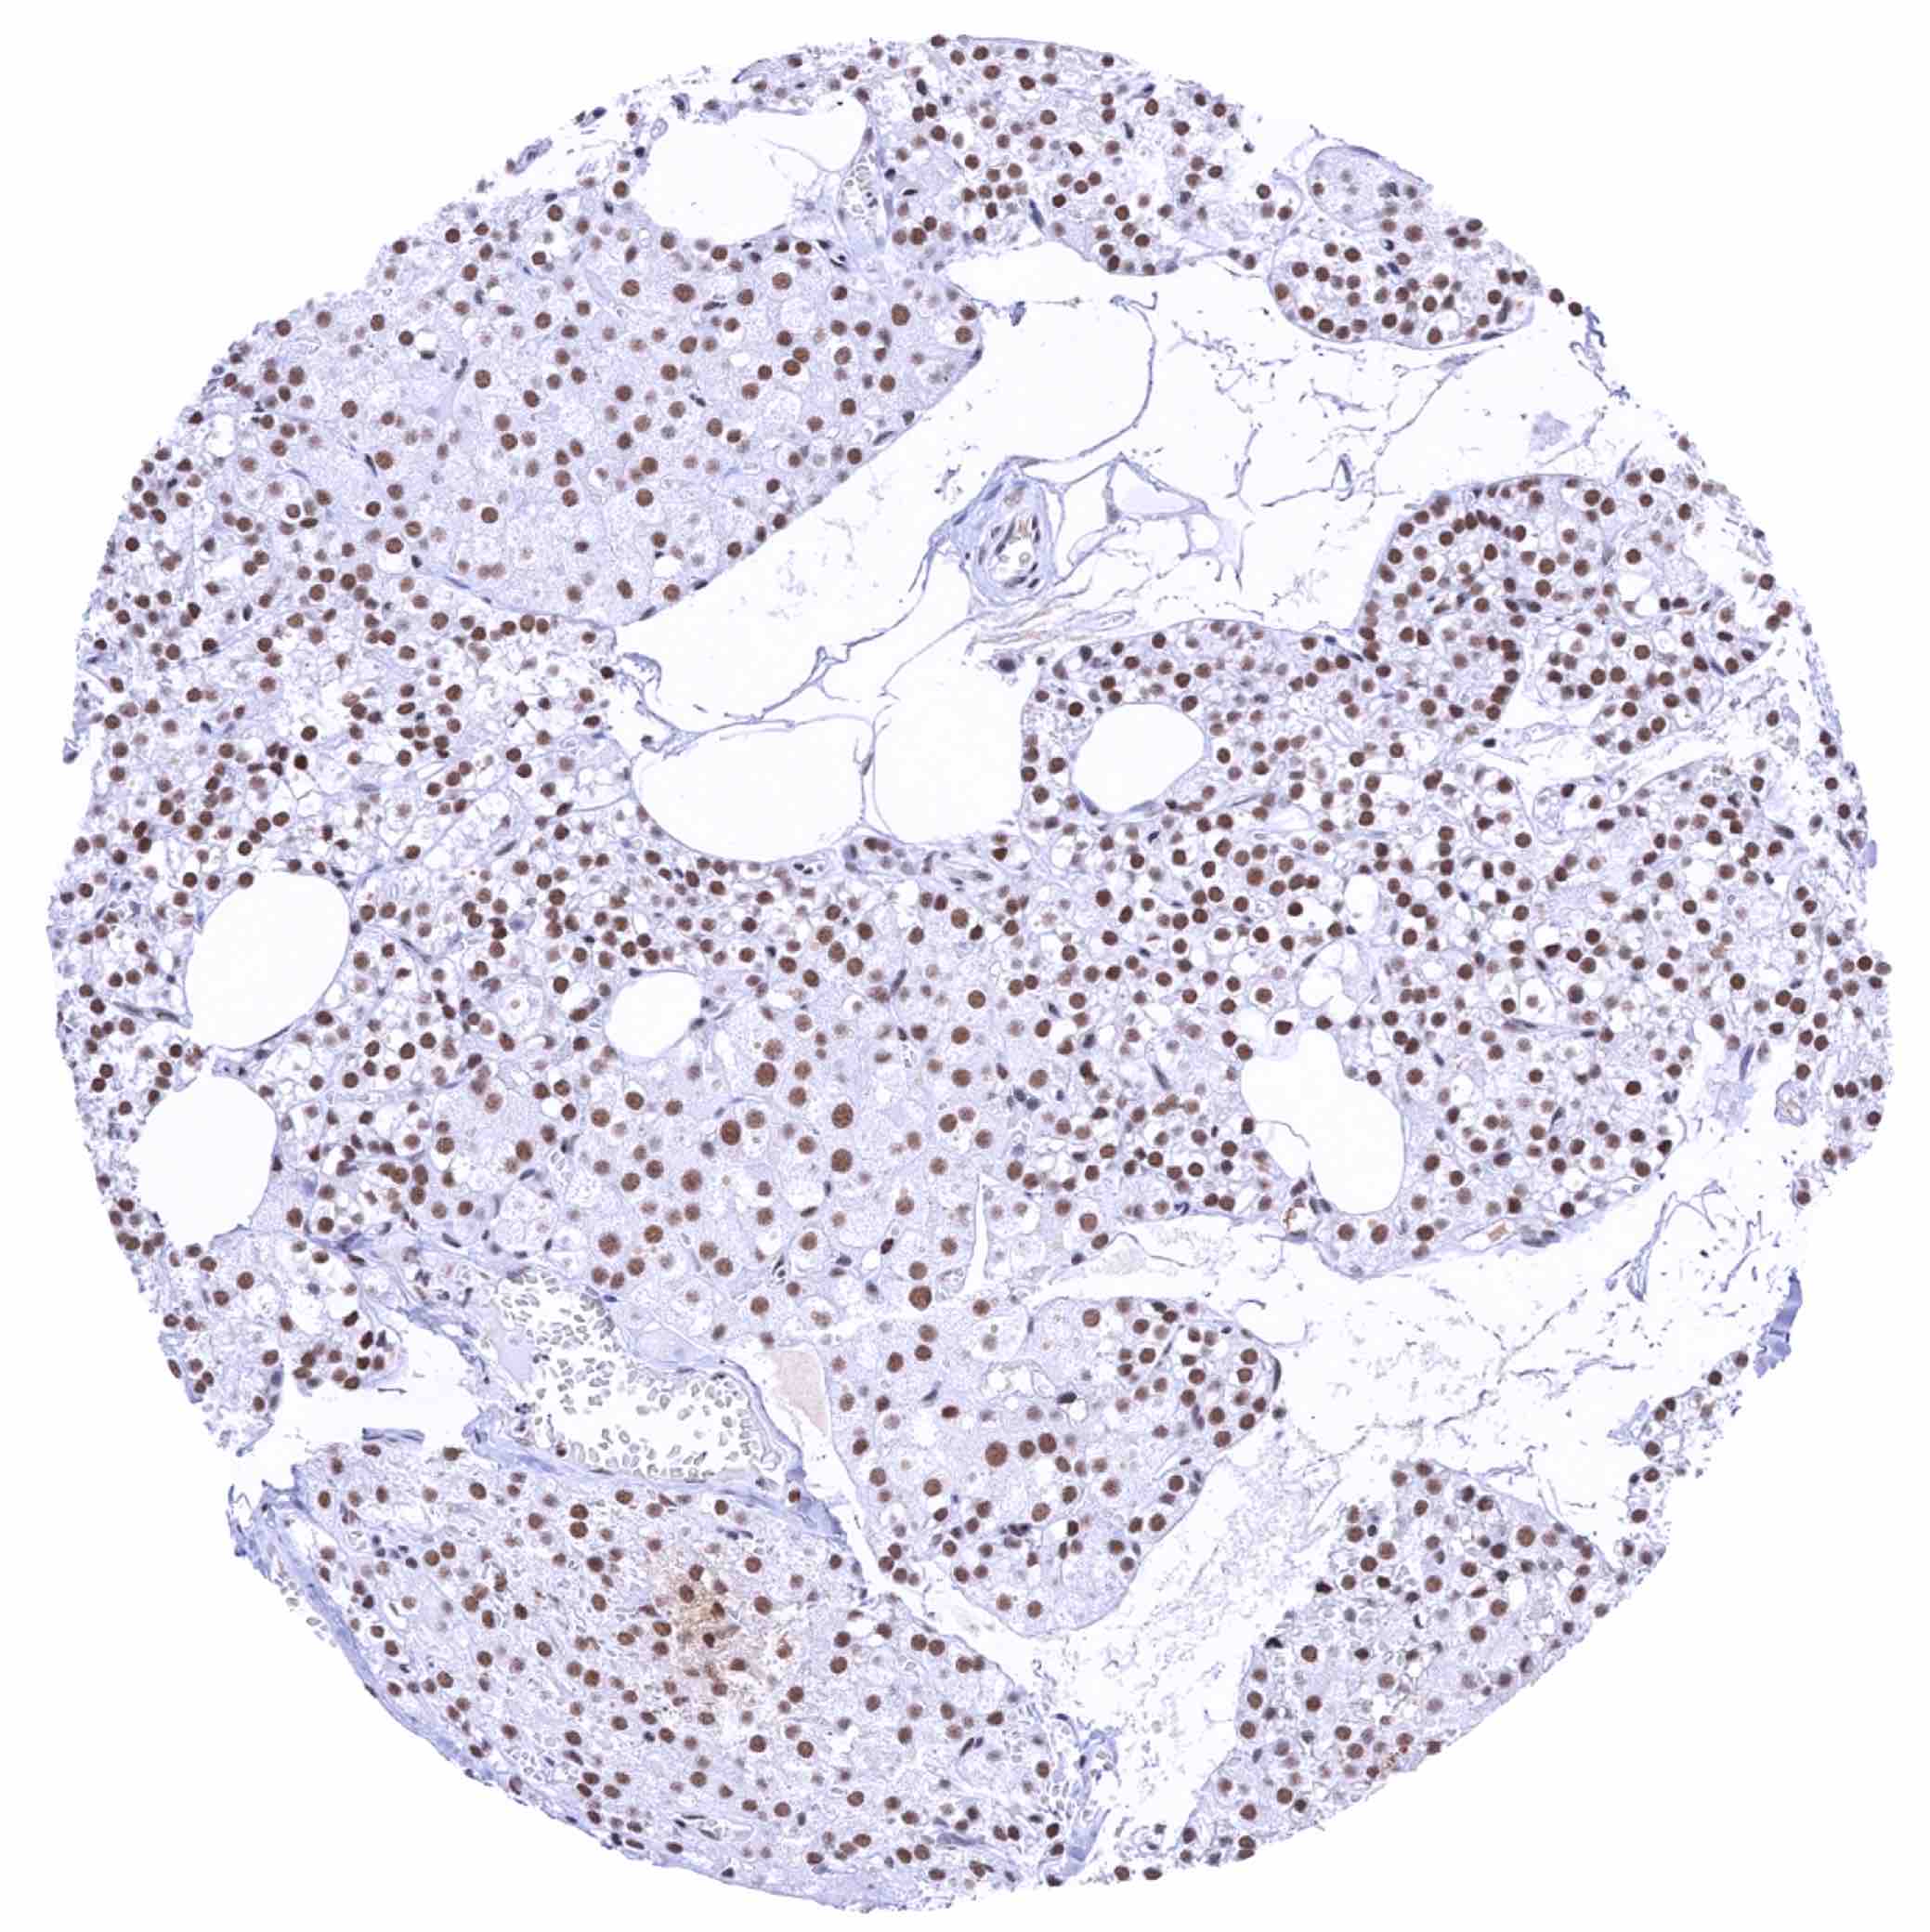

Lymph node – Moderate to strong staining of lymphocytes and other cell types